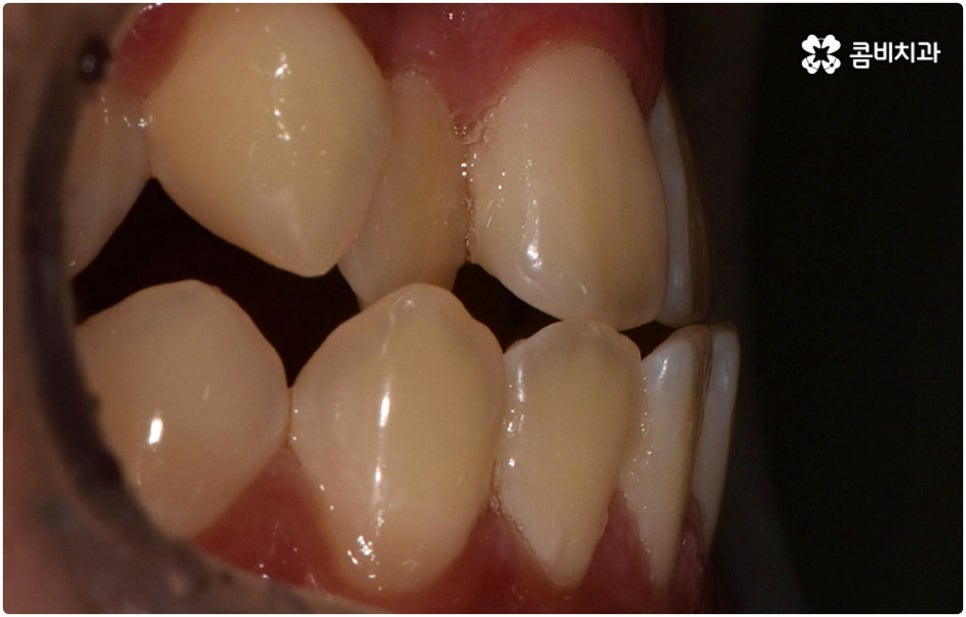

부정교합은 부정교합 1급, 부정교합 2급, 부정교합 3급 이렇게 세가지 종류로 나눌 수 있는데요. 부정교합 1급은 이를 다물었을 때 위아래 어금니는 잘 맞물리지만 덧니가 있거나 치아 사이가 살짝 벌어져 있는 경우처럼 치열이 삐뚤어진 경우를 말하는 것으로 골격이나 구조적인 부분에는 크게 문제가 없기 때문에 정도가 심하지 않다면 보다 빠르고 간편한 교정 치료가 가능한 케이스라고 할 수 있어요. 부정교합 2급은 상악이 하악보다 더 튀어나온 상태로 위에서 언급했던 무턱, 돌출입이 여기에 속하며 반대로 부정교합 3급 은 주걱턱처럼 하악이 상악보다 튀어나온 상태를 의미하고 있습니다.

부정교합 2급, 부정교합 3급 과 같이 구조적인 부분에 원인이 있는 문제라면 잇몸뼈가 다 굳고 난 다음인 중장년 성인분들의 경우 교정 치료를 받는 것이 과연 부정교합 개선에 효과가 있을까 궁금해 하실 수 있어요. 특히 턱관절 이상 문제는 수술을 통해서만 고칠 수 있다고 알고 계셨던 분들은 부담을 느끼고 치료를 미루셨을 수 있는데요. 물론 성인분들의 경우 상황에 따라, 예를 들어 정도가 매우 심한 부정교합 3급 케이스라면 악교정수술을 받아야 할 수도 있습니다. 또한 대부분의 부정교합 2급, 부정교합 3급 케이스들 같은 경우 초등학교 고학년에서 중학교 저학년 사이에 교정 치료를 시작하는 것이 좋다고 권유하는 것도 사실인데요, 그 이유는 아무래도 치아 이동 속도가 빠르고 전반적인 발달 상황에 맞추어 자연스럽게 치료를 진행할 수 있는 성장기의 특성상 이 시기부터 지속적으로 턱뼈 크기 부조화를 조절하고 상하악의 올바른 성장을 유도하는 게 보다 효율적이기 때문이라고 할 수 있어요.